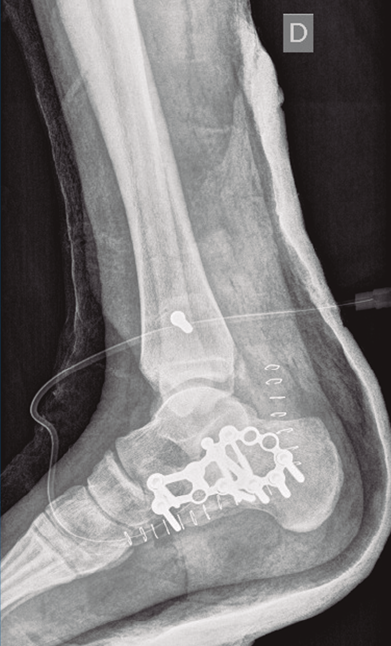

Figura 9. Control radiográfico posquirúrgico, anteroposterior.

Figura 10. Control radiográfico posquirúrgico, lateral.

Se dio de alta el día siguiente a la cirugía con un buen control analgésico. En la radiografía de control postoperatoria presentó una correcta reducción tanto de la fractura de calcáneo como de la articulación tibioperoneo astragalina (Figuras 9 y 10). Se citó en consultas externas 2 semanas después para la retirada de la sutura, presentado un buen aspecto las heridas quirúrgicas (Figura 11), y para la colocación de un botín de yeso. Dicho botín fue retirado al mes y medio de la cirugía, colocándose una ortesis estabilizadora de tipo Walker y autorizándose la carga parcial y progresiva, comenzando la rehabilitación.